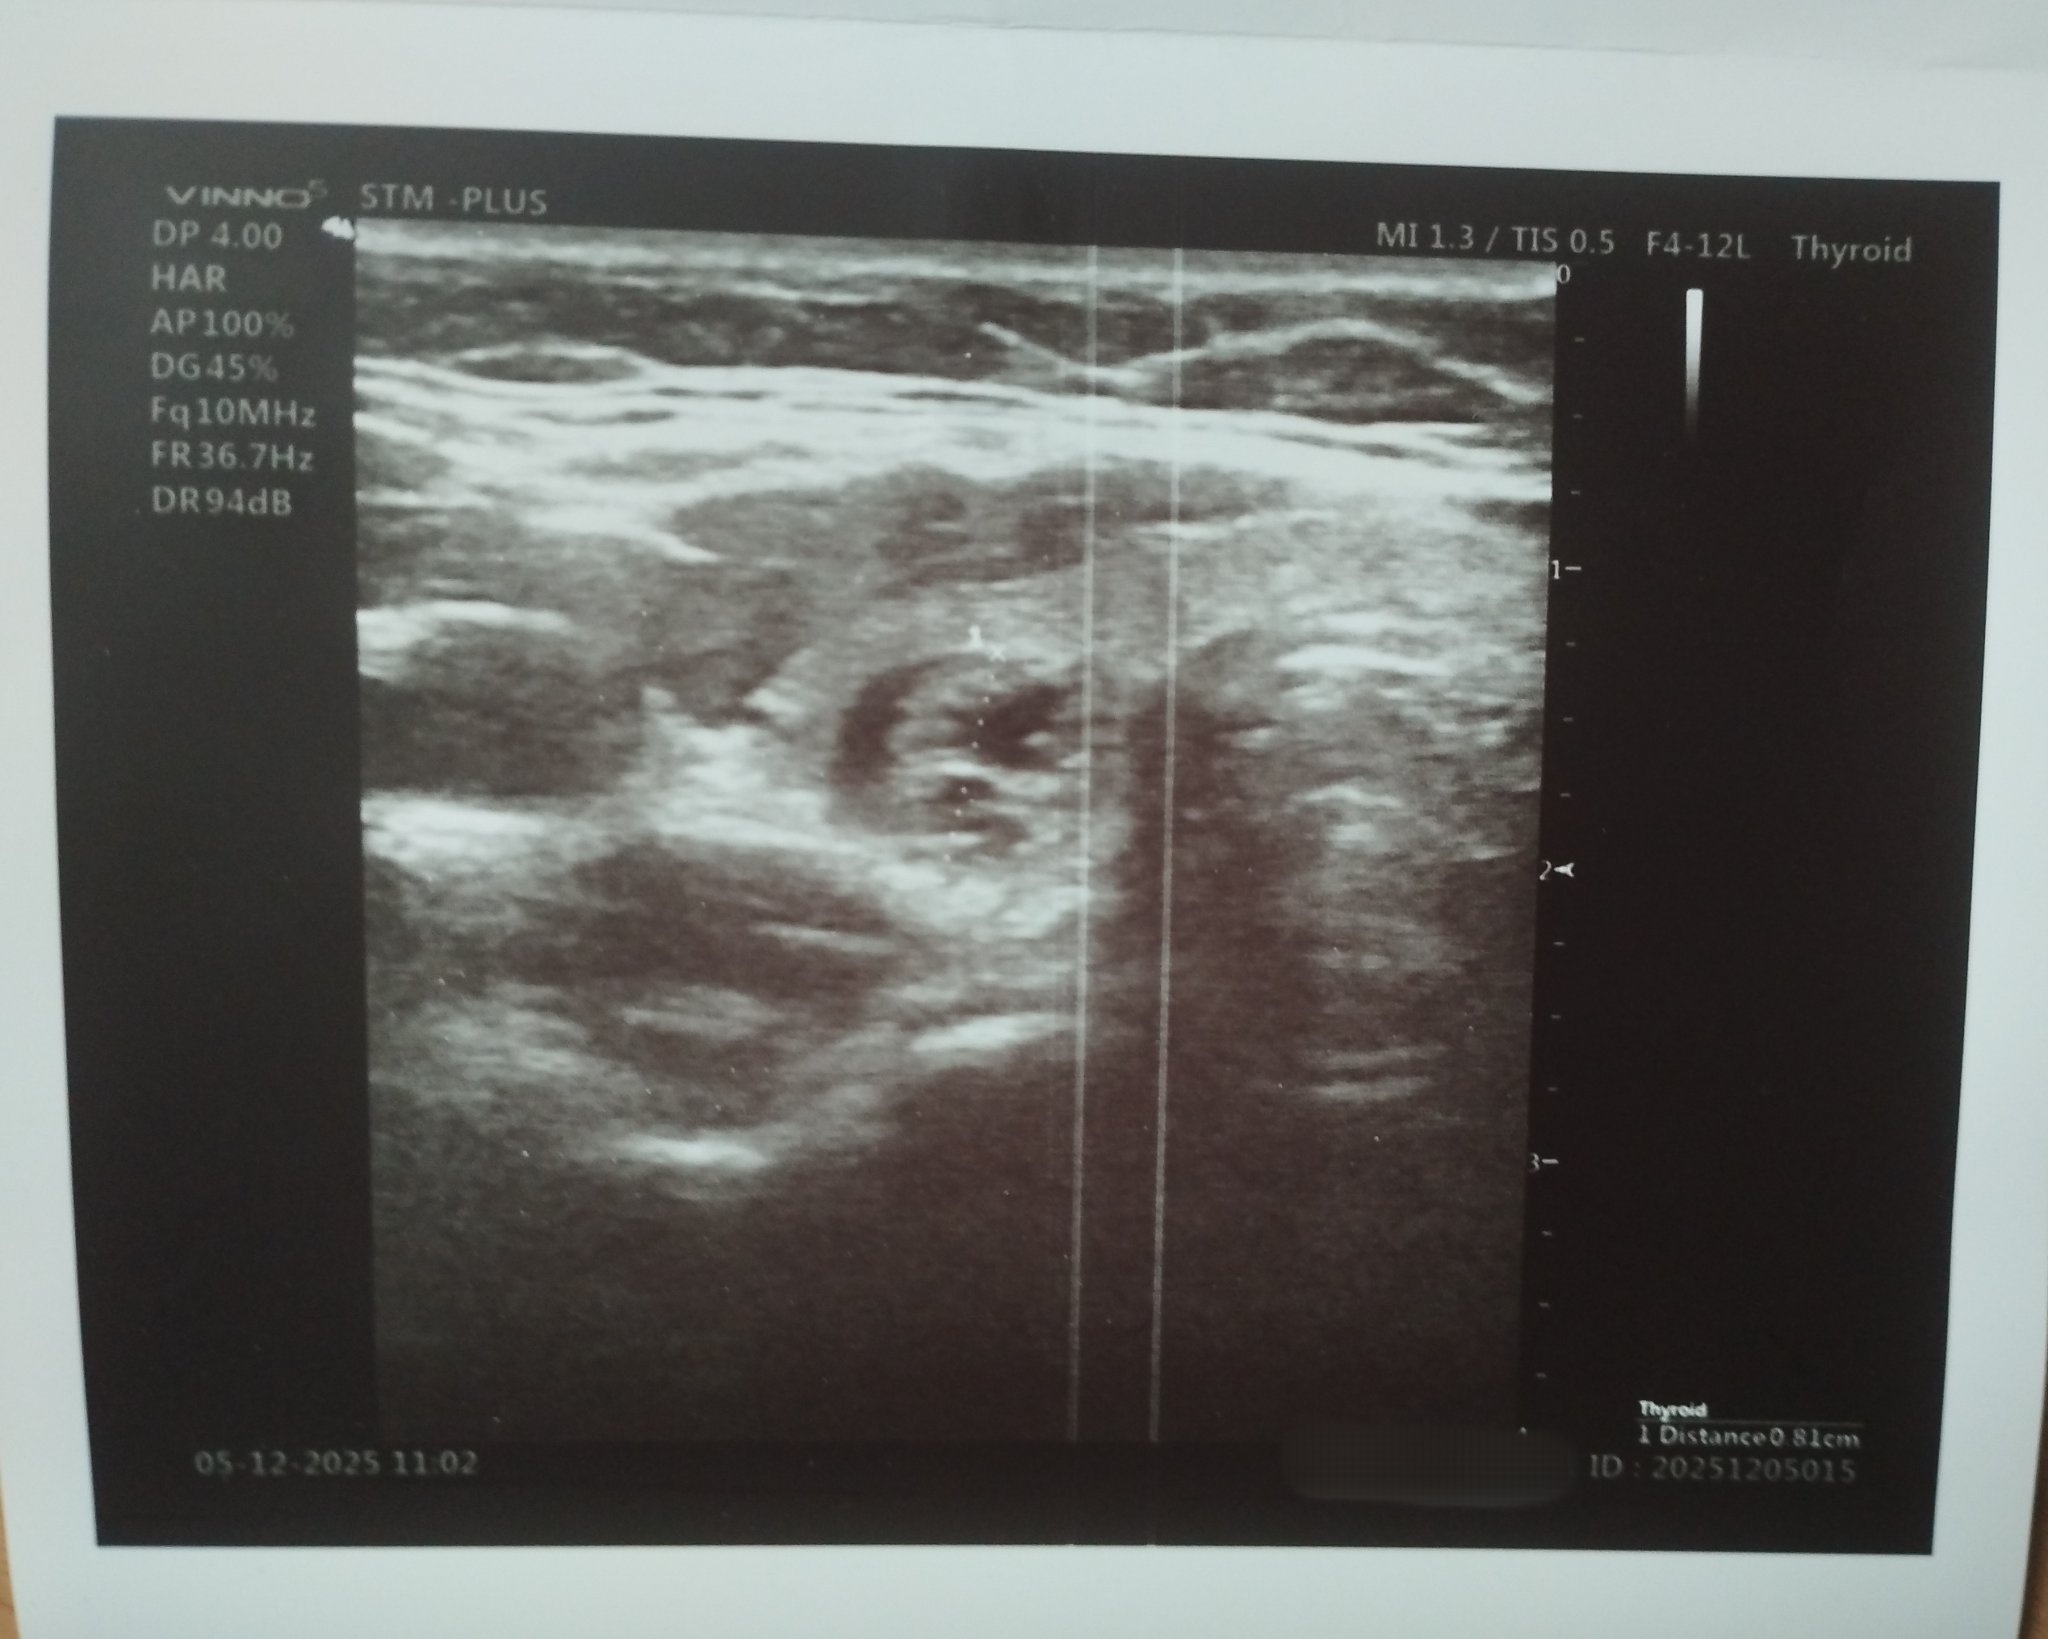

Здравейте,

при медицински преглед на работното място ми откриха възел на щитовидната жлеза.

Не можах да запомня колко е голям,но лекаря ми каза,че не е нещо притеснително - да отида при ендокринолог

Може ли някой, който разбира да ми разчете резултатите написани на снимката /колко е голям този възел/,че малко се притесних